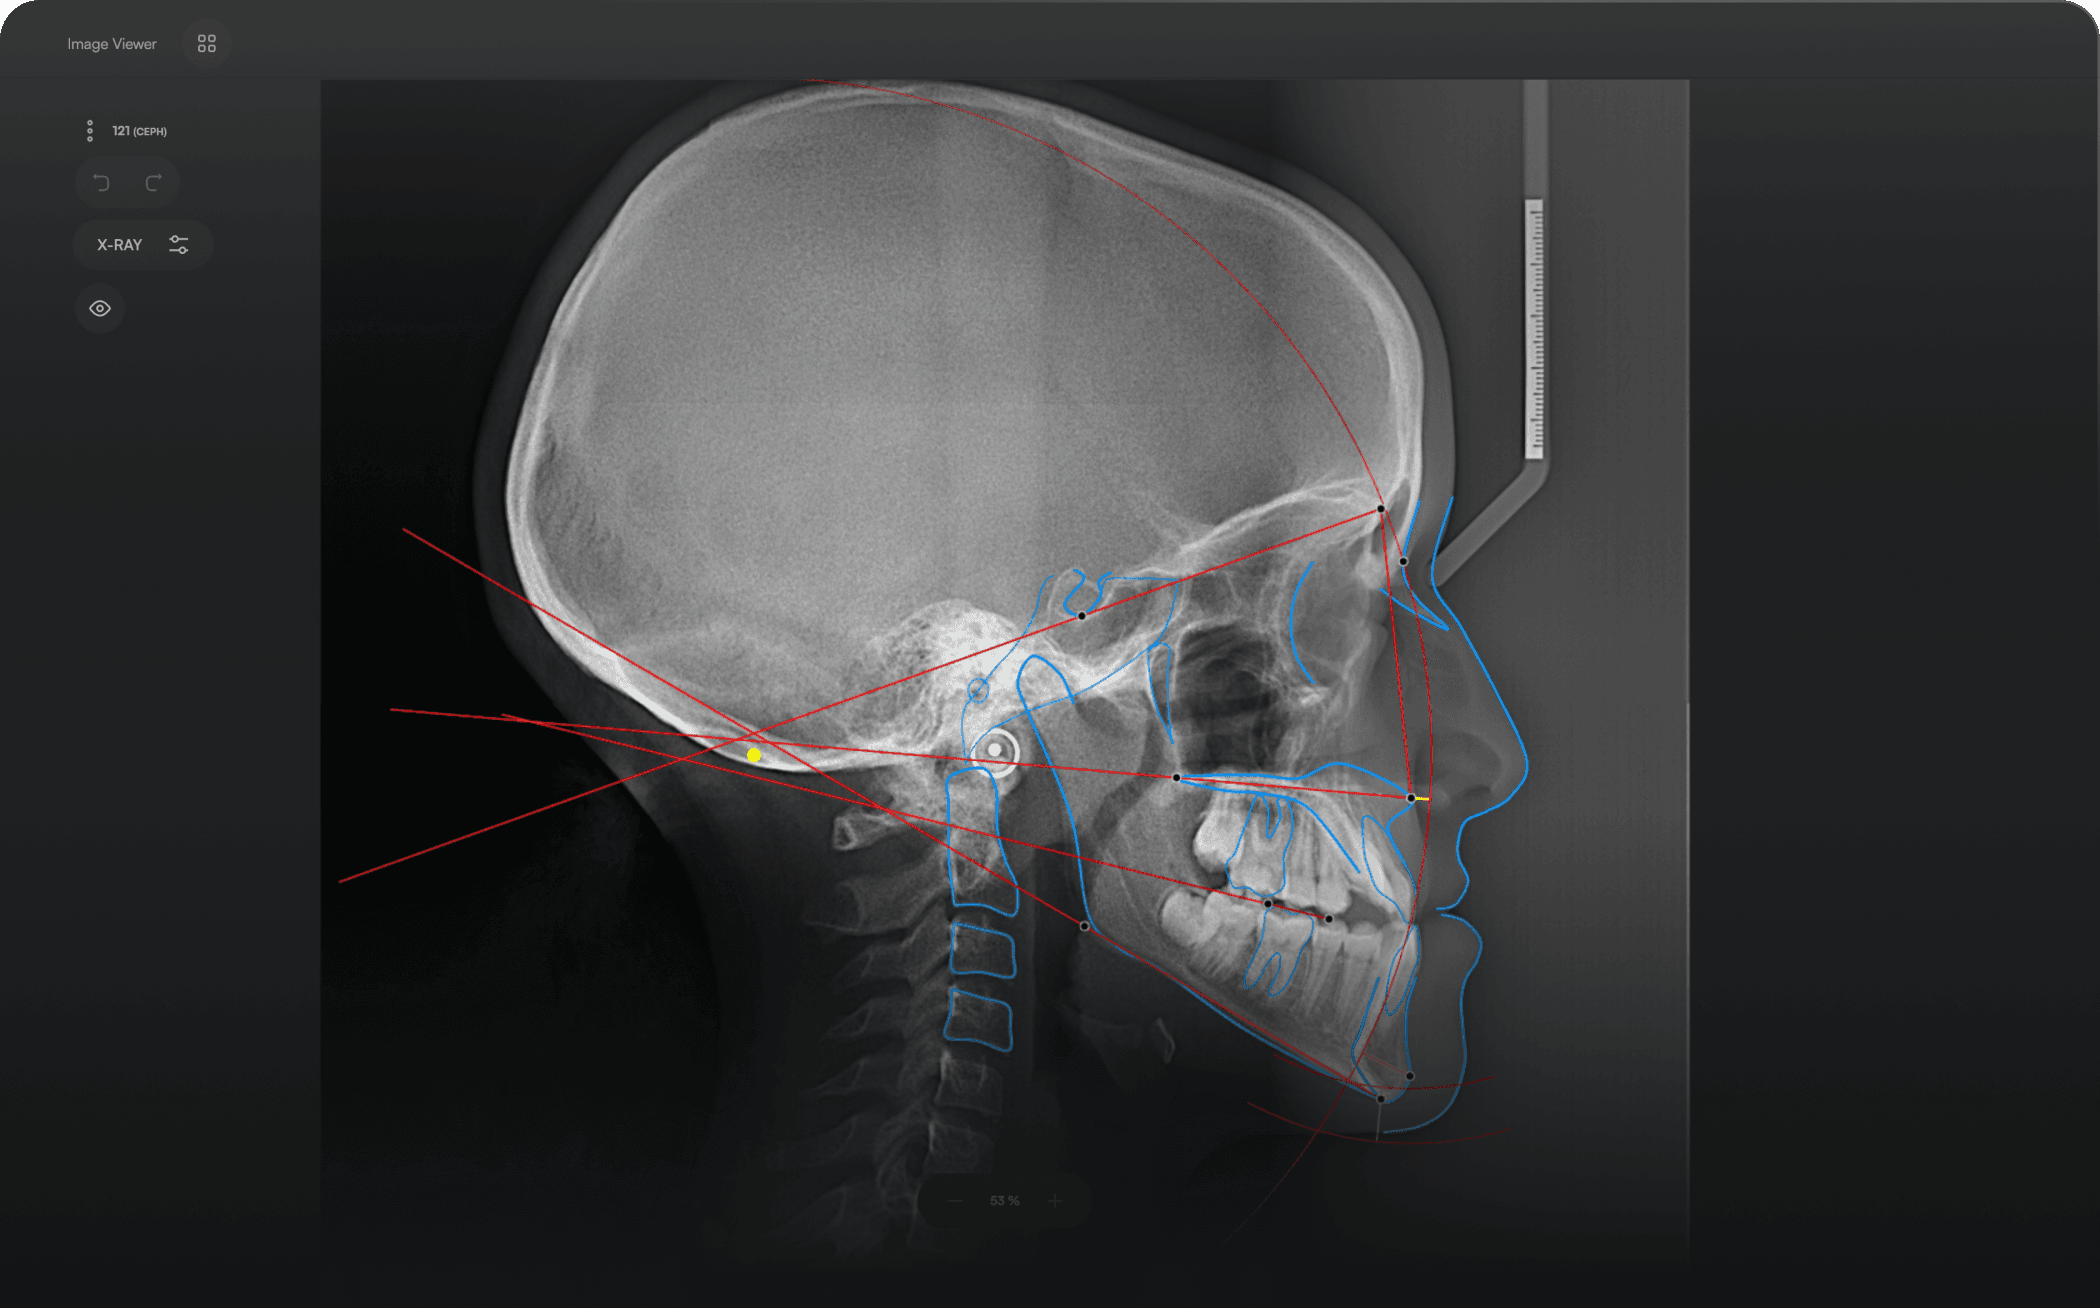

Diverse Analysis

Access automated studies like Steiner and Jefferson to assist in clinical assessment and enhance case evaluations.

Powerful Insights

Experience a comprehensive assessment of skeletal, dental, and soft tissue discrepancies.

Run AI

Let the software handle tracing and reporting

3